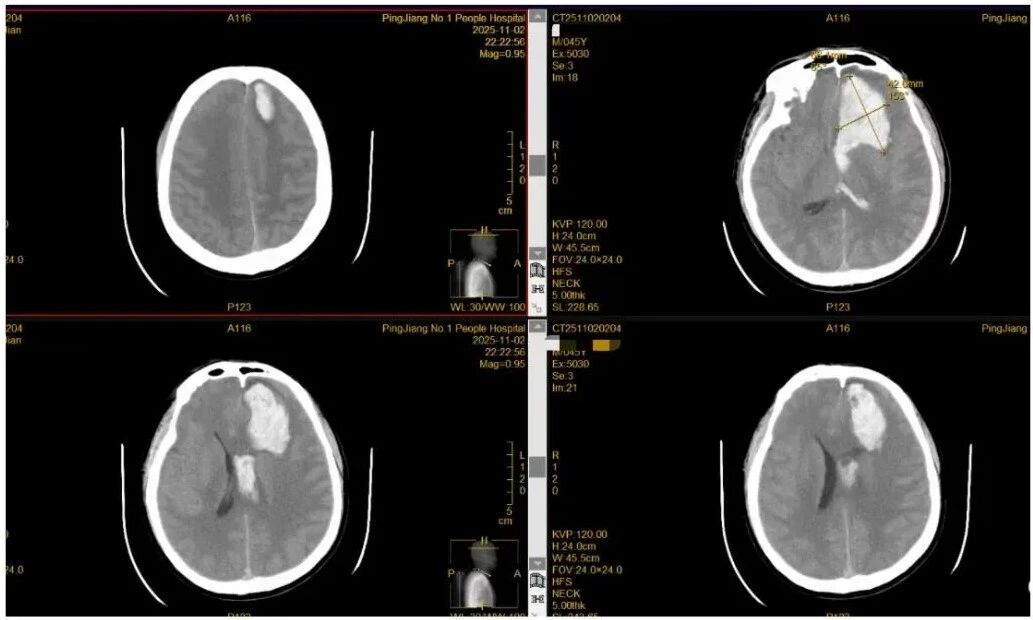

到院首诊:急诊医生同步接收院前急救信息,快速判断病情后,立即安排头颅CT检查,报告显示颅内出血;

紧急会诊:神经外科医生第一时间会诊,随即完善头颅CTA检查,明确诊断——左侧额叶脑出血(出血量约100ml),周围脑组织受压明显,需紧急手术;

(▲图片说明:入院时颅脑CT显示颅内出血)